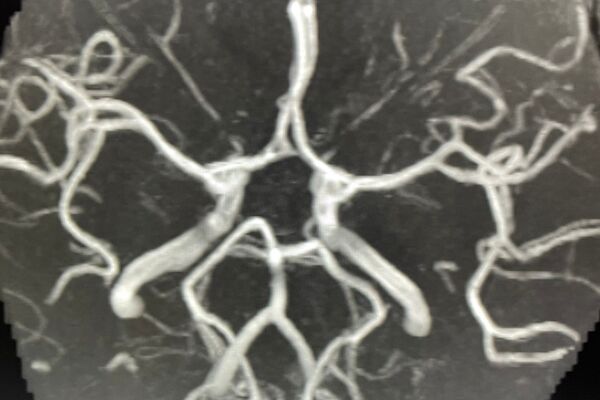

Das Aufgabengebiet der Neuroradiologie umfasst die Diagnostik von Erkrankungen und Veränderungen des Zentralen Nervensystems (ZNS), d.h. von Gehirn und Rückenmark. Das Gehirn ist ein äußerst komplexes Organ des menschlichen Körpers, so dass die Neuroradiologie eine mehrjährige Spezialisierung im Fachgebiet Radiologie erfordert, die vergleichbar mit der Kardiologie im Fachgebiet der Inneren Medizin oder der Gehirnchirurgie im Fachbereich der Chirurgie ist.

Diagnostik und Befundung in der Radiologie sind im Verlauf der letzten Jahre immer komplexer und anspruchsvoller geworden. Mit der spezialisierten Neuroradiologischen Diagnostik bieten wir Ihnen in unserer Praxis eine besondere Expertise in der Auswertung Ihrer Untersuchungen an.

Beispiele für spezielle Neuroradiologische Fragestellungen:

4. Abklärung von Kopfschmerzen, Schwindel, Tinnitus, Hör- und Sehstörungen usw.

5. Ursachenforschung bei Lähmung der Gesichtsmuskeln (Facialisparese), Schmerzzuständen der Gesichtshaut (Trigeminusneuralgie) oder Schädigungen der übrigen Hirnnerven